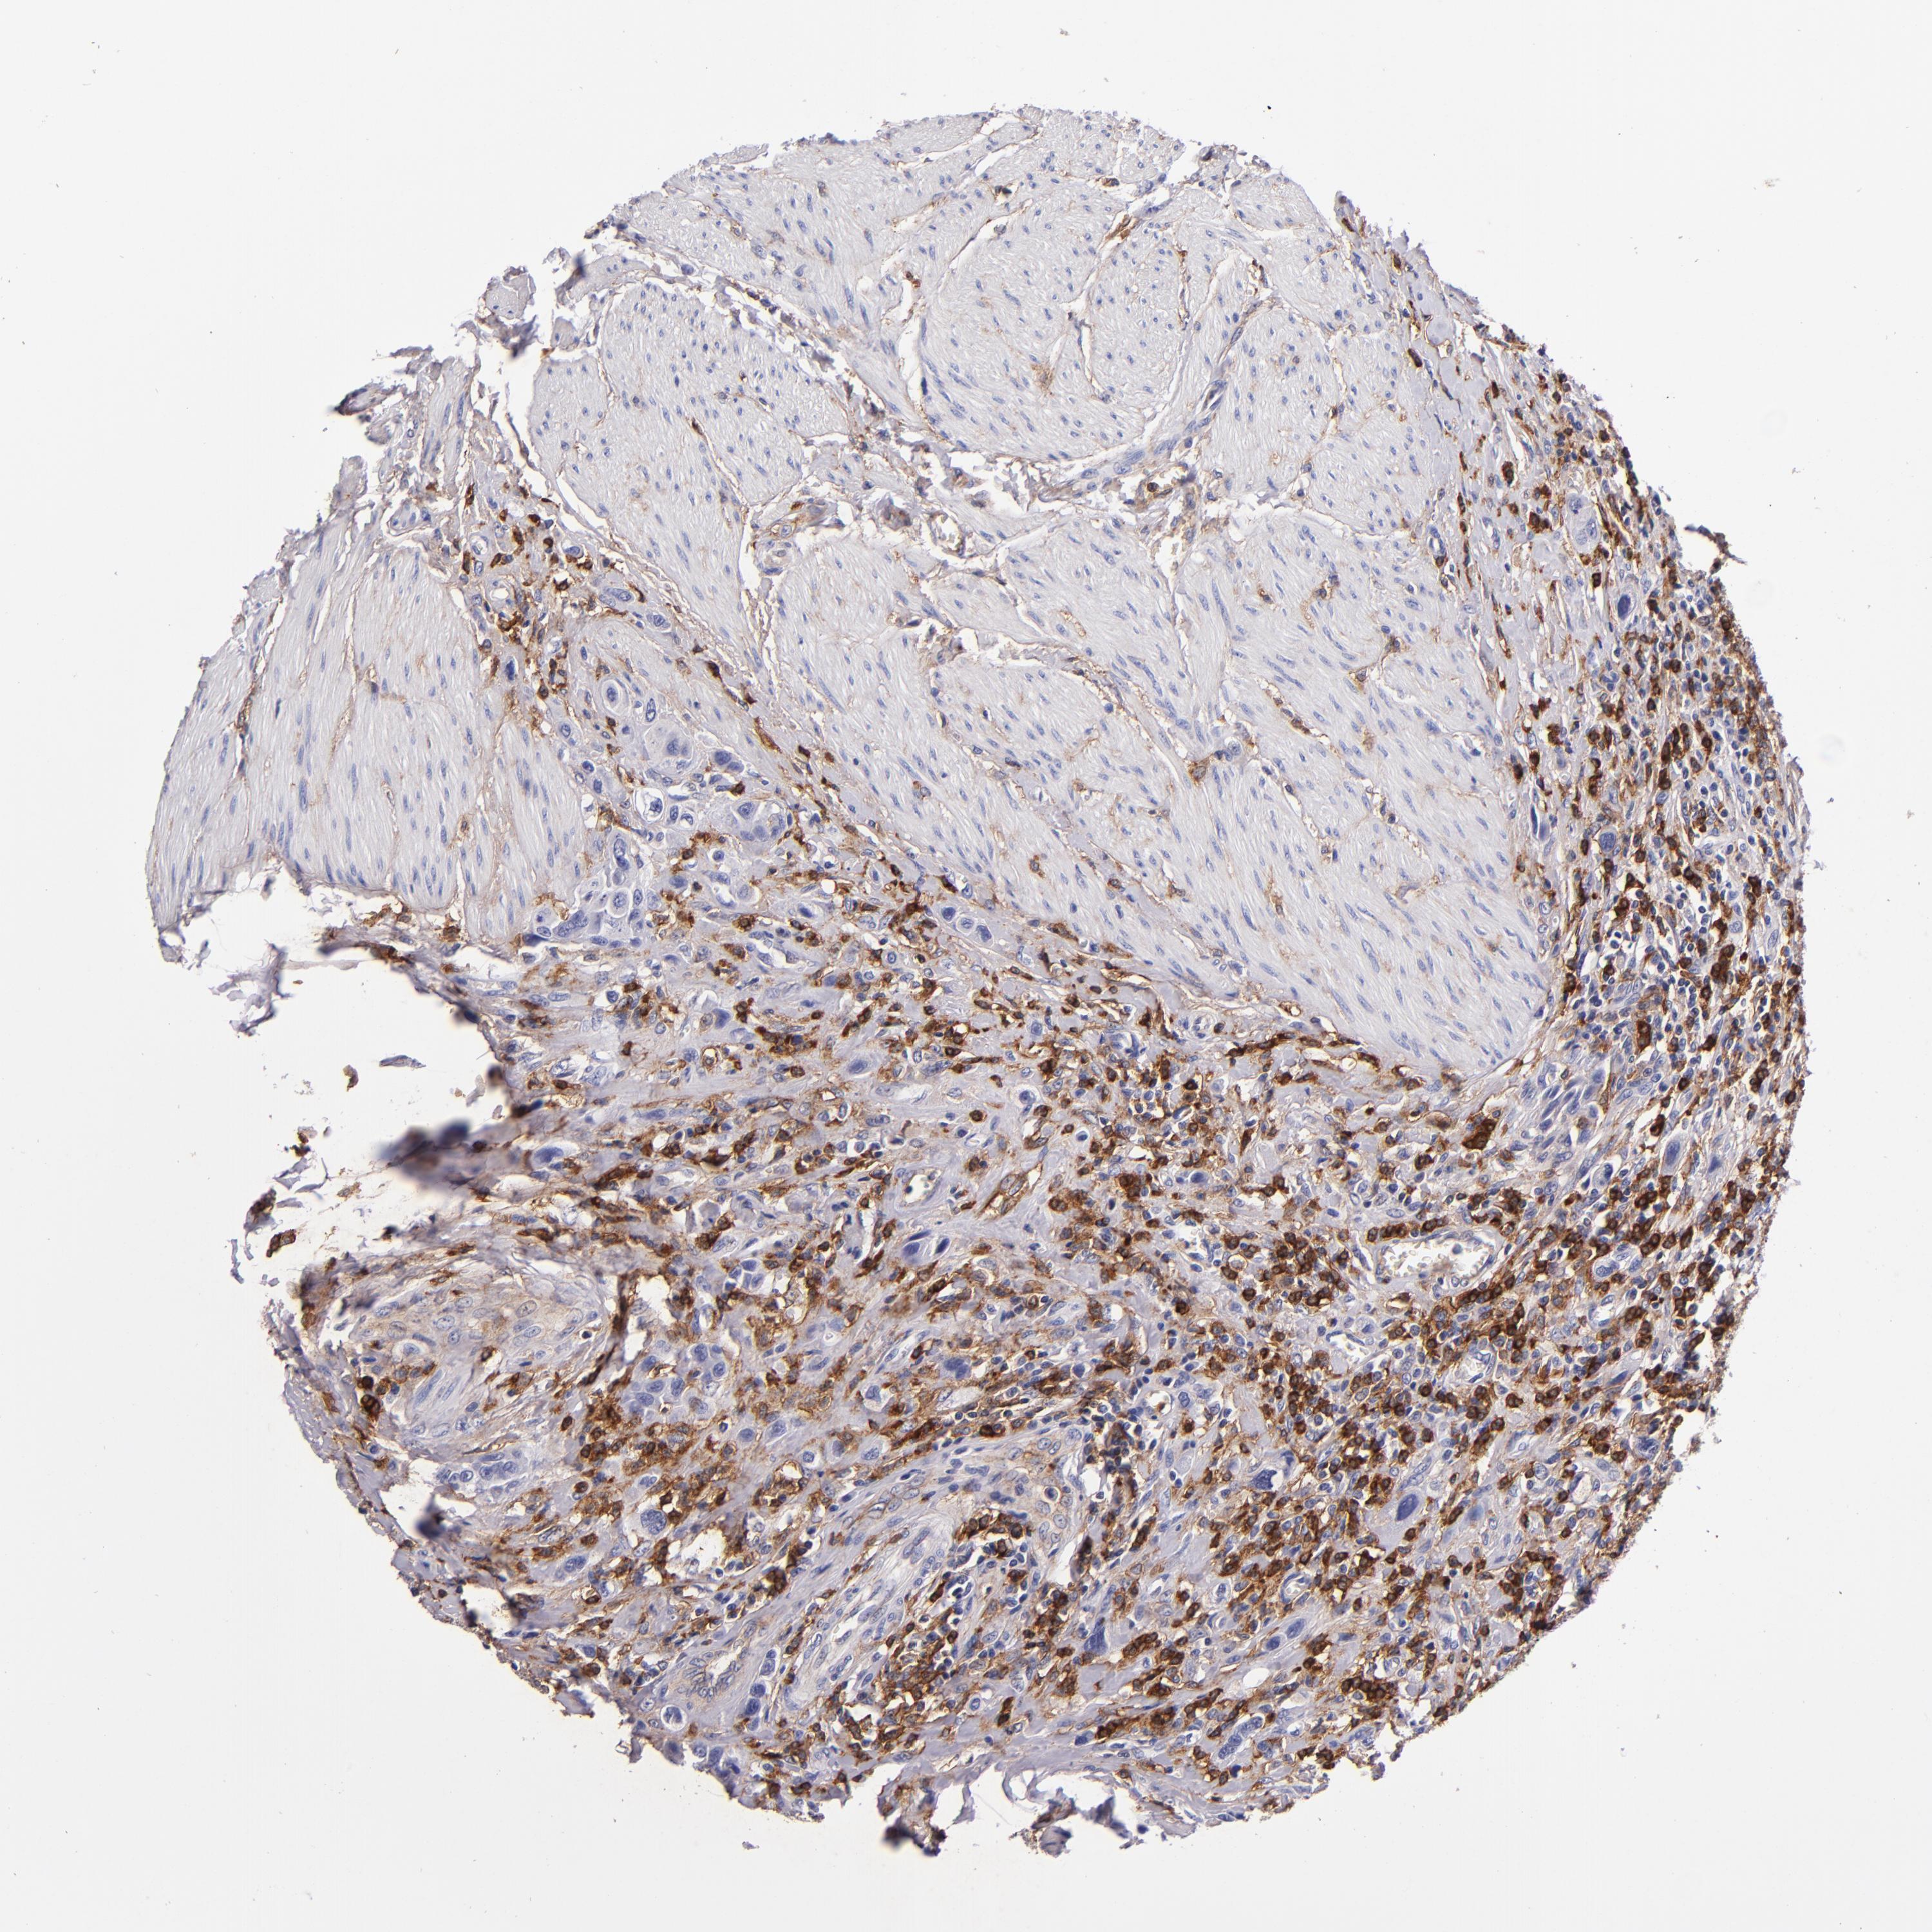

UROTHELIAL CANCER - Protein expressioni

A mouse-over function shows sample information and annotation data. Click on an image to view it in a full screen mode. Samples can be filtered based on level of antibody staining by selecting one or several of the following categories: high, medium, low and not detected. The assay and annotation is described here.

Note that samples used for immunohistochemistry by the Human Protein Atlas do not correspond to samples in the TCGA dataset.

Antibody stainingi

Antibody staining in the annotated cell types in the current human tissue is reported as not detected, low, medium, or high, based on conventional immunohistochemistry profiling in selected tissues. This score is based on the combination of the staining intensity and fraction of stained cells.

Each image is clickable and will lead to virtual microscopy that enables deeper exploration of all samples and also displays staining intensity scores, fraction scores and subcellular localization as well as patient and tissue information for each sample.

Antibody HPA054437

Antibody HPA058511

Antibody CAB002776

Antibody CAB015122

Staining

High

Medium

Low

Not detected

Intensity

Strong

Moderate

Weak

Negative

Quantity

>75%

75%-25%

<25%

None

Location

Nuclear

Cytoplasmic/membranous

Cytoplasmic/membranous,nuclear

Urothelial carcinoma, High grade

Urothelial carcinoma, Low grade

Urothelial carcinoma, NOS